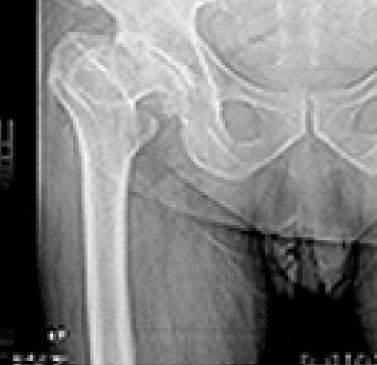

Hip Fracture Fixation

Hip fracture fixation is a surgical procedure designed to treat and stabilize a broken hip, which typically affects the femoral neck